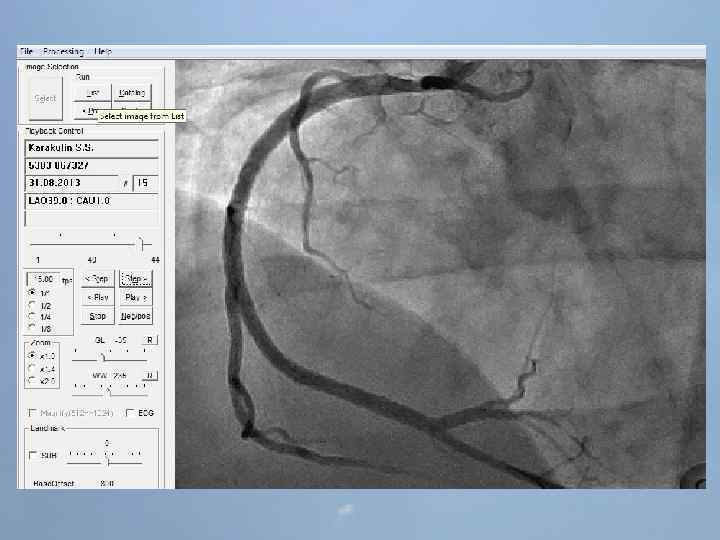

Пациент Б. , 54 года 29. 08. 13 около 10: 00, находясь на рабочем месте, почувствовал боль в груди. После 2 -ух приемов нитроспрея боль не уменьшилась, вызвал СМП. В 10: 20 первой бригадой СМП зафиксирован подъем ST на ЭКГ, начата ТЛТ, вызвана реанимационная бригада. В 10: 50 на месте вызова в присутствии реаниматолога у пациента развивается остановка кровообращения по типу фибрилляции желудочков. Выполнялась СЛР с непрямым массажем сердца, ИВЛ мехом, дефибрилляцией. В течение транспортировки фибрилляция рецидивировала еще 4 раза. Пациент доставлен в ООКБ в 11: 30, минуя приемное отделение госпитализирован в ОРИТ ОИМ.

Проведенные мероприятия: Обезболивание – морфин 1%-1 мл; Введена полная доза пуролазы – 6 млн МЕ; Дана нагрузочная доза клопидогрела - 300 мг; Начата в/в инфузия гепарина – 1000 МЕ/час; Дофамин 4% - в/в через ДЛВ; С противоаритмической целью: Кордарон 300 мг болюсом, затем 600 мг – капельно; Лидокаин 120 мг в/в; Магния сульфат 25% - 15 мл в/в; Калия хлорид 5% - 10 мл в/в.